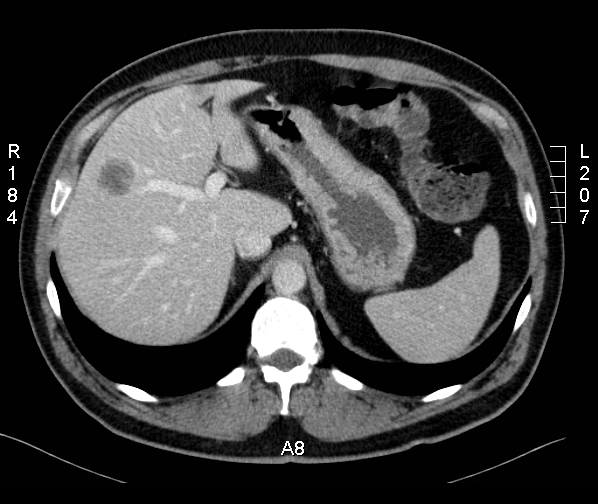

A CT scan of thorax, abdomen and pelvis confirmed a markedly enhancing mass in segment 6 of the liver, measuring about 3 cm (Figure 1 [Fig. 1]). Additional colonoscopy was without pathological findings. FNAC (fine needle aspiration cytology) was performed revealing a well-differentiated chondroid sarcoma with a proliferation index (Ki67) of 10%. Histology was confirmed by a pathology reference service. Based on the histological diagnosis a PET-CT scan and skeletal scintigraphy were undertaken revealing no pathological FDG uptake. Without evidence of any extrahepatic primary the tumor was classified as a sarcoma of hepatic origin. Comprehensive chemical and haematological laboratory did not reveal any pathologic finding. Values for AFP, CEA and CA 19-9 were within normal ranges as well. Since there were no signs of non-resectability the patient was admitted for surgery. Due to the preoperative histology of a chondroid sarcoma a right hemihepatectomy was performed in order to include the biopsy channel resulting in a 15 x 14 x 9.5 cm resection specimen. The tumor was completely resected with a distance of 1.2 cm to the resection margin and 0.9 cm to the liver surface, respectively. Macroscopically the tumor on the cut surface appeared grossly, grayish-white, measuring 3.5 x 2.7 x 2.6 cm. On (immuno-) histological examination the lesion was paucicellular revealing a substantial eosinophilic matrix (Alcian-positive) and a cartilaginous component (Figure 2 [Fig. 2]). Chondroid cells were positive for Vimentin and focally positive for S100 antigen (Figure 3 [Fig. 3]). Ki67 staining showed a proliferation index <1% (0/50 HPF), p53 was completely negative. At the margin the tumor showed remarkable proliferation of bile ducts (CK 7 positive) and interspearsed capillary vessels (CD 34 positive). Given these histologic findings molecular-cytogenetic investigations were performed to further characterise the tumor. Comparative genomic hybridisation revealed neither gain nor loss of chromosomal material. In absence of any signs of malignancy the final diagnosis of a chondroid hamartoma of the liver was made.

Figure 1: CT scan showing a solid liver tumor measuring ~3 cm